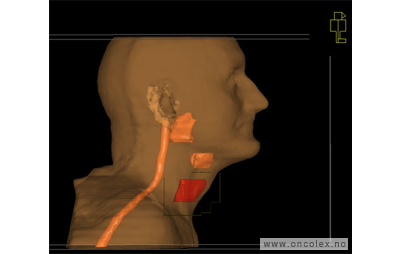

Skisse over hvordan strålefeltet planlegges:

Illustrasjon for målvolum

• GTV (Gross Tumor Volume): Identifisert tumor.

• CTV (Clinical Target Volume) GTV + omkringliggende vev hvor det kan væremikroskopisk spredning.

• ITV (Internal Target Volume): CTV + en indre margin som tar hensyn tilindre bevegelser og endringer av CTV.

• PTV (Planning Target Volume): Innstillingsmargin som inneholder ITV og samtidig tar hensyn til antatte pasientbevegelser, samt variasjoner i pasientopplegging og feltinnstillinger.

• Feltgrense. Tegnes som oftest på kroppen.

ICRU (International Commission on Radiation Units and Measurements)